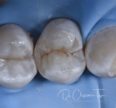

Fissure pattern variations on a maxillary first molar

Cute fissure forms on the amalgam removal for this molar #happymolar #GC #EssentiaU